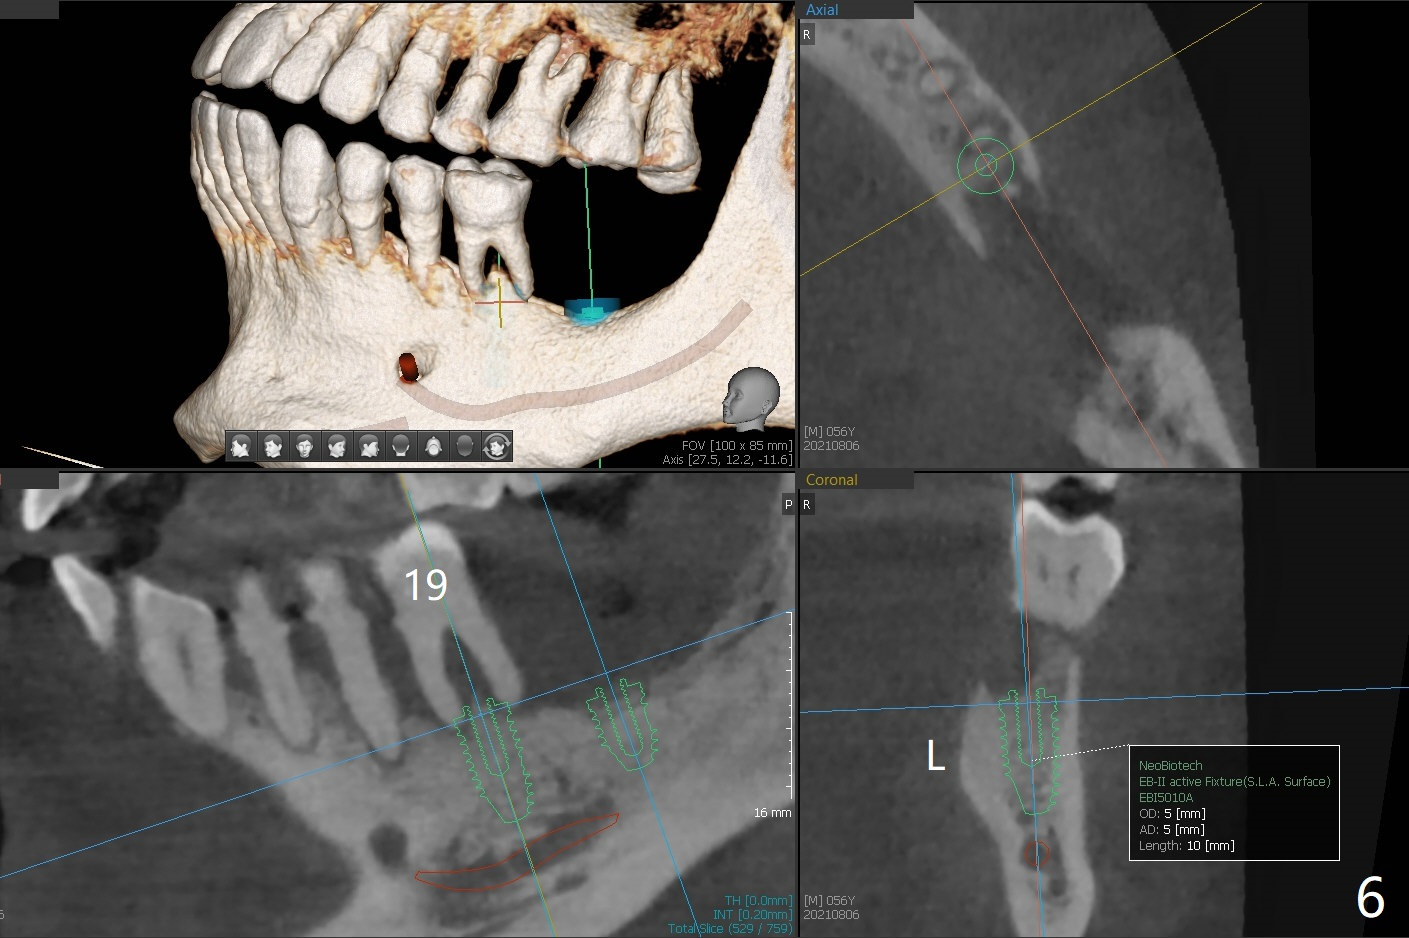

56岁男几十年拒绝牙周炎治疗,也不愿意拔除所有牙齿做全口植牙修复。17,18号牙自行脱落,现在要求拔除16,19;18,19种植(图一),后者牙龈厚(双箭头),但是18号牙骨质高度不足(图二),勉强植入5x7.3毫米植体。15,16骨质吸收严重(图三),16,19拔除,局部深洗后(图四:黑色),为了延长15号牙使用期,16号牙牙槽窝植骨(图五:红色)。19号牙种植徒手,因为邻牙(包括20,21号牙))松动,做导板不准确,钻洞使用环形钻头(图六),保留骨塞(bone plug),用于18号牙骨质高度骨块移植。19号牙拔除后,往远中18牙位做潜行分离(图七:黑色)。19种植(绿色),基台(粉红色),骨粉(圆圈),临时牙冠(白色),16号牙粘性骨粉植骨(红色),PRF,Cytoplast覆盖(白线),缝合。从19号牙钻洞取来的骨塞,塞入18号牙潜行分离处(图八);利用临时牙冠和22号牙以及钢丝,树脂固定20,21号牙(蓝色),并且降低咬合(*)。最后,用螺钉固定骨塞(图九:深蓝色)。